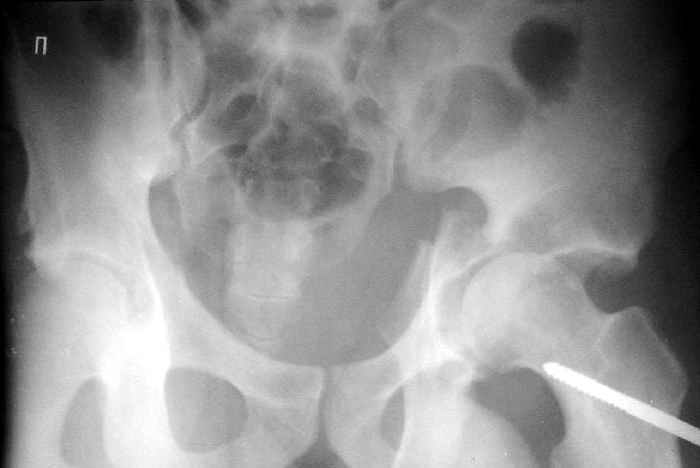

Пациент переведен в нашу клинику на 5 день после множественной травмы 25.01.2003 - двустороннее повреждение вертлужных впадин, разрыв левого

крестцово-подвздошного сочленения. Вывихи обоих бедер. В месте первичного поступления подвздошный вывих правого бедра вправлен

26.01.2003, наложено вытяжение за левую вертельную область.

Остеосинтез левой вертлужной впадины выполнен у нас 6.02.2003.

Вопрос: надо ли синтезировать задне-верхний край правой вертлужной впадины?